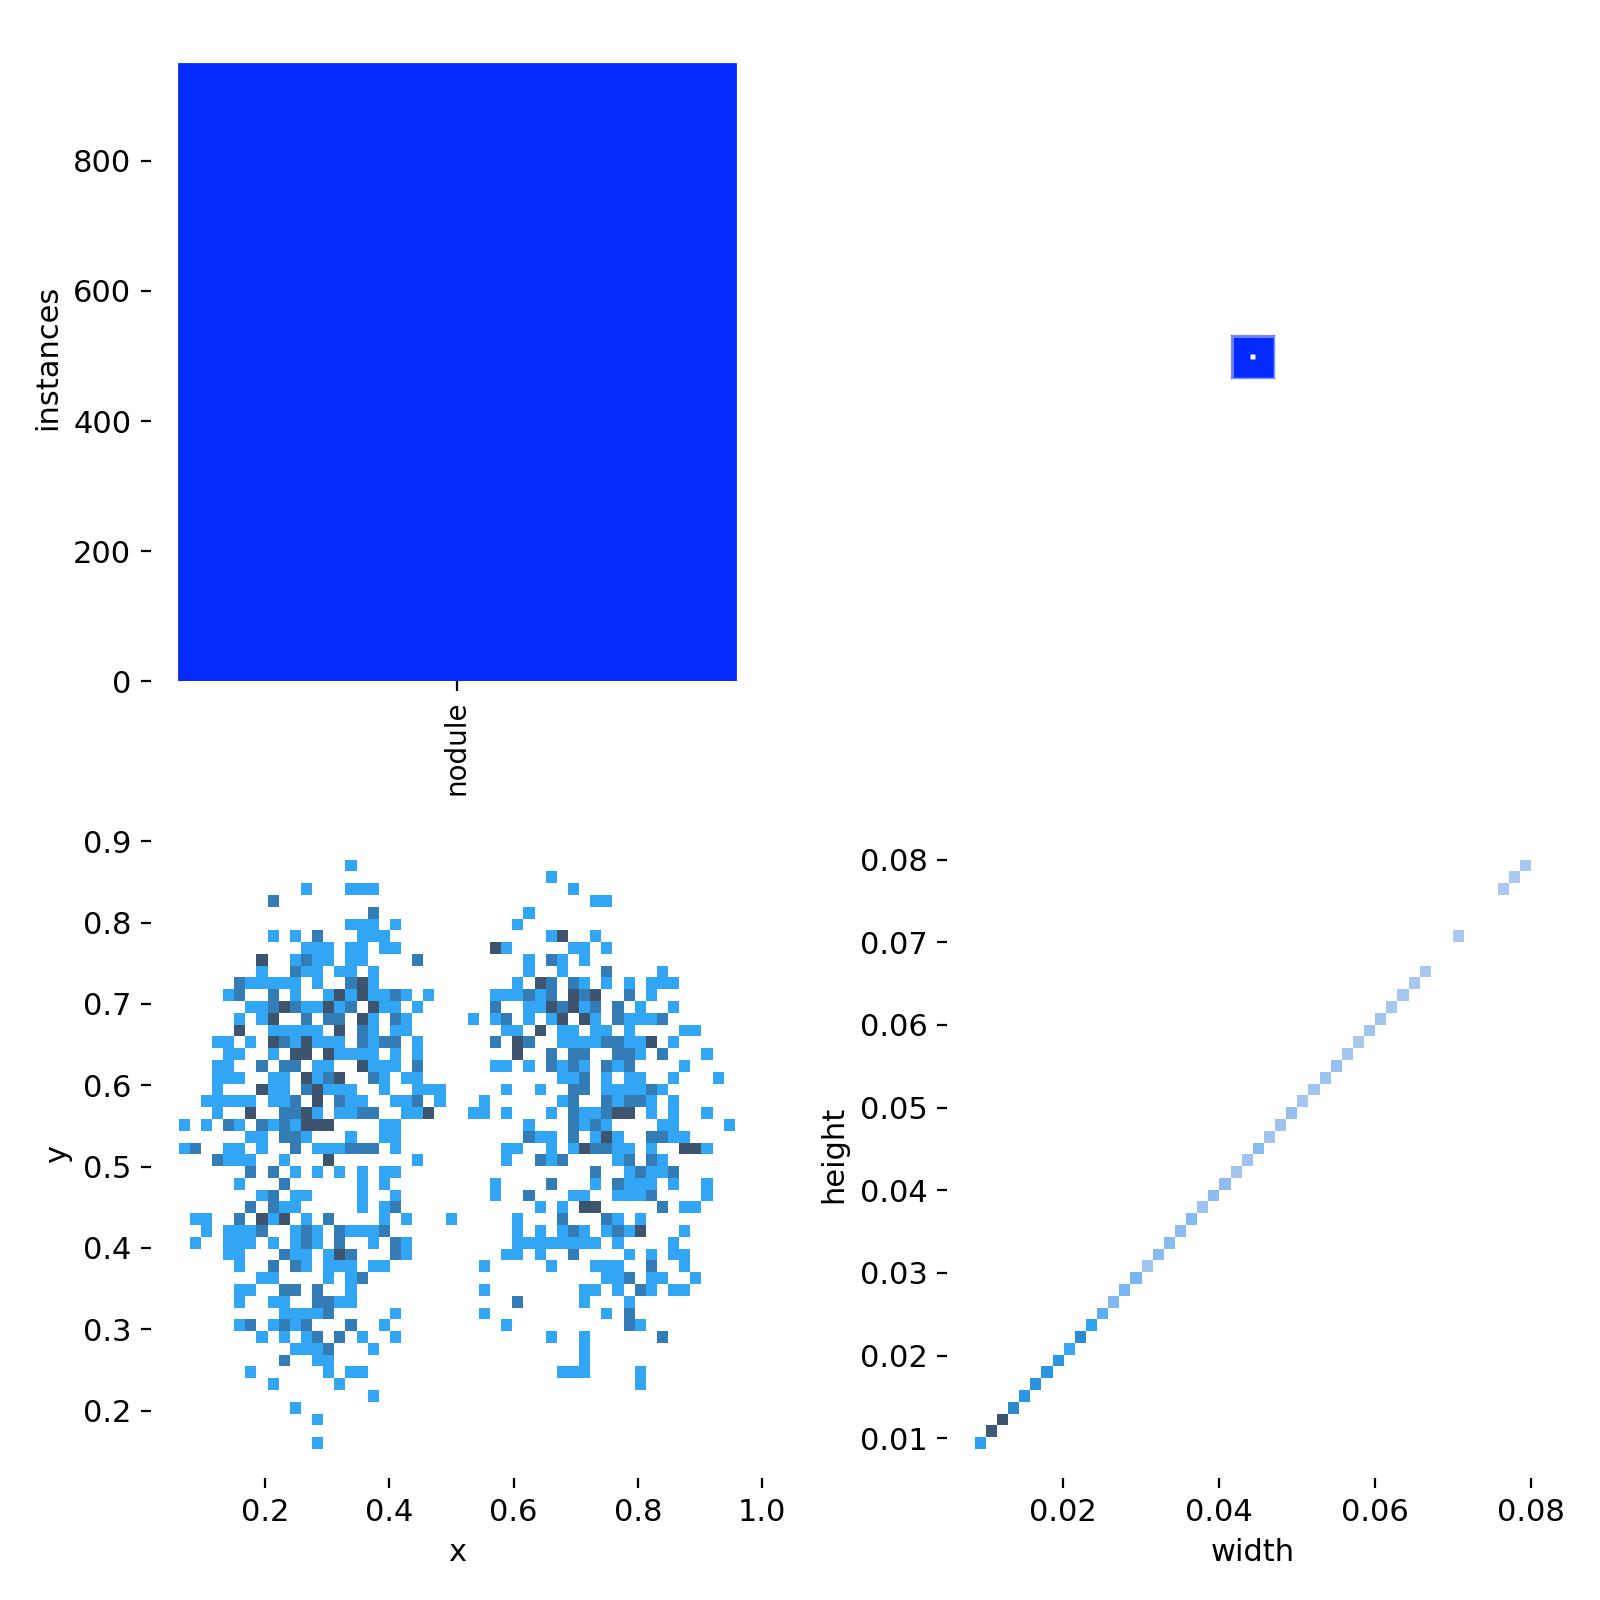

以及下面是数据集中每个类别对应的实例数量和边界框大小的基本分析,从下图可以看出,大部分目标都比较小,属于是小目标检测的内容。